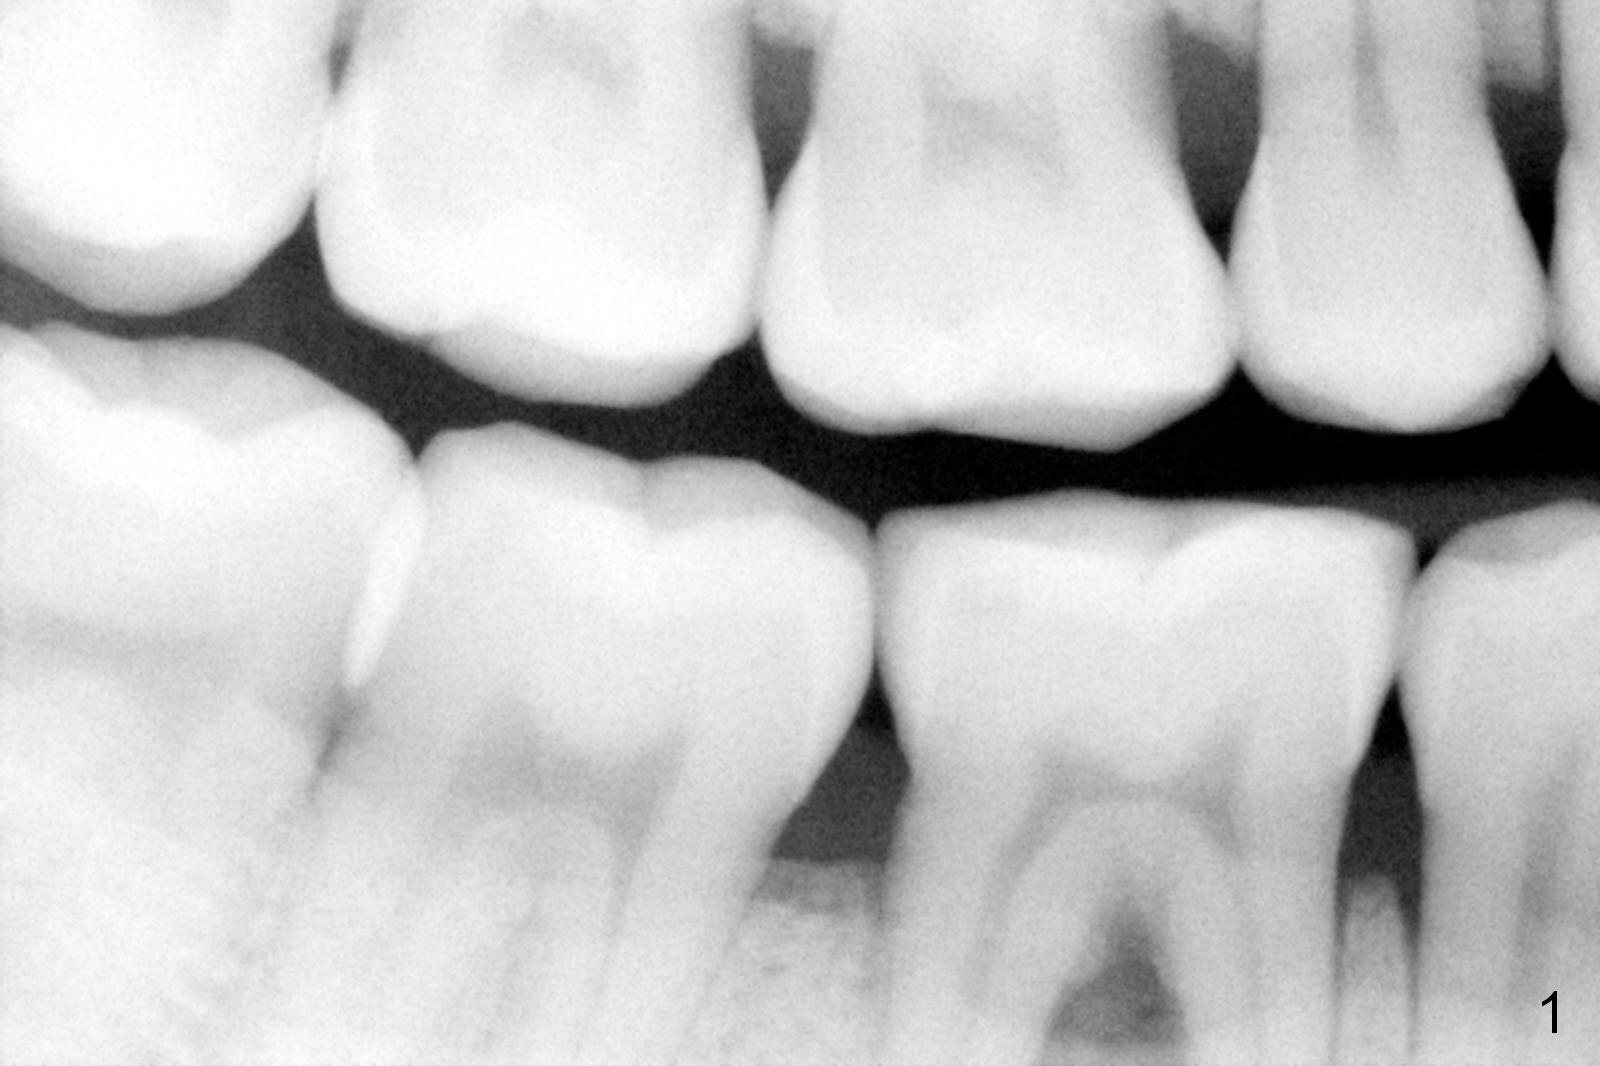

A 45-year-old man had Class I or II furcation involvement at the tooth #30 ten years ago (Fig.1, Classifications of Furcation Involvement - Stedman's Online). He returns recently requesting composite to seal Class IV furcation involvement (Fig.2). It appears that the tooth is unsalvageable (Fig.3 (no Antibiotic)). Since it is difficult to differentiate the upper (yellow dashed line) vs. the lower (brown line) borders of the Inferior Alveolar Canal, the initial depth will be 8 mm. Take panoramic X-ray if necessary. Because of severe bone loss, an abutment with 6 mm cuff is to be used (Pink area).